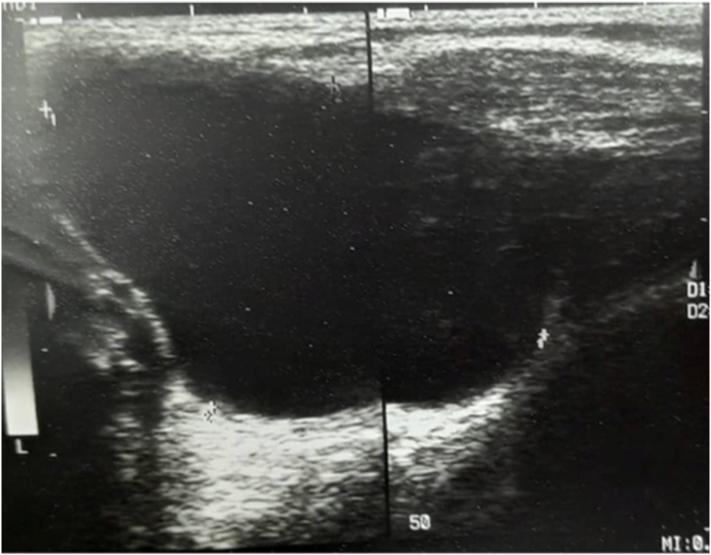

Here we report a case of axillary cystic hygroma in a 6-year-old healthy boy, which presented with the rapid development of a right axillary mass during 3 days, without any predisposing factor.

Cystic hygromas occur due to complete or partial obstruction of lymphatic vessels, which leads to lack of communication with the venous system, this results in the accumulation of lymphatic fluid and swelling, it occurs in the cervicofacial region most of the time 75 %, but it can arise anywhere in the body, it classically presents as painless, soft mass, diagnosis can be done using ultrasound, CT, MRI, each of which has its advantages, surgical treatment is routinely favored, but other options are also available.

我们在此报告一例6岁健康男孩的腋窝囊状水瘤,该患儿在3天内右腋窝肿块迅速增大,无任何诱发因素。

囊状水瘤是由于淋巴管完全或部分阻塞,导致与静脉系统缺乏连通,从而引起淋巴液积聚和肿胀。它大多发生在颈面部区域(75%),但也可出现在身体的任何部位,典型表现为无痛性、柔软肿块。可通过超声、CT、MRI进行诊断,每种方法都有其优点。常规首选手术治疗,但也有其他选择。